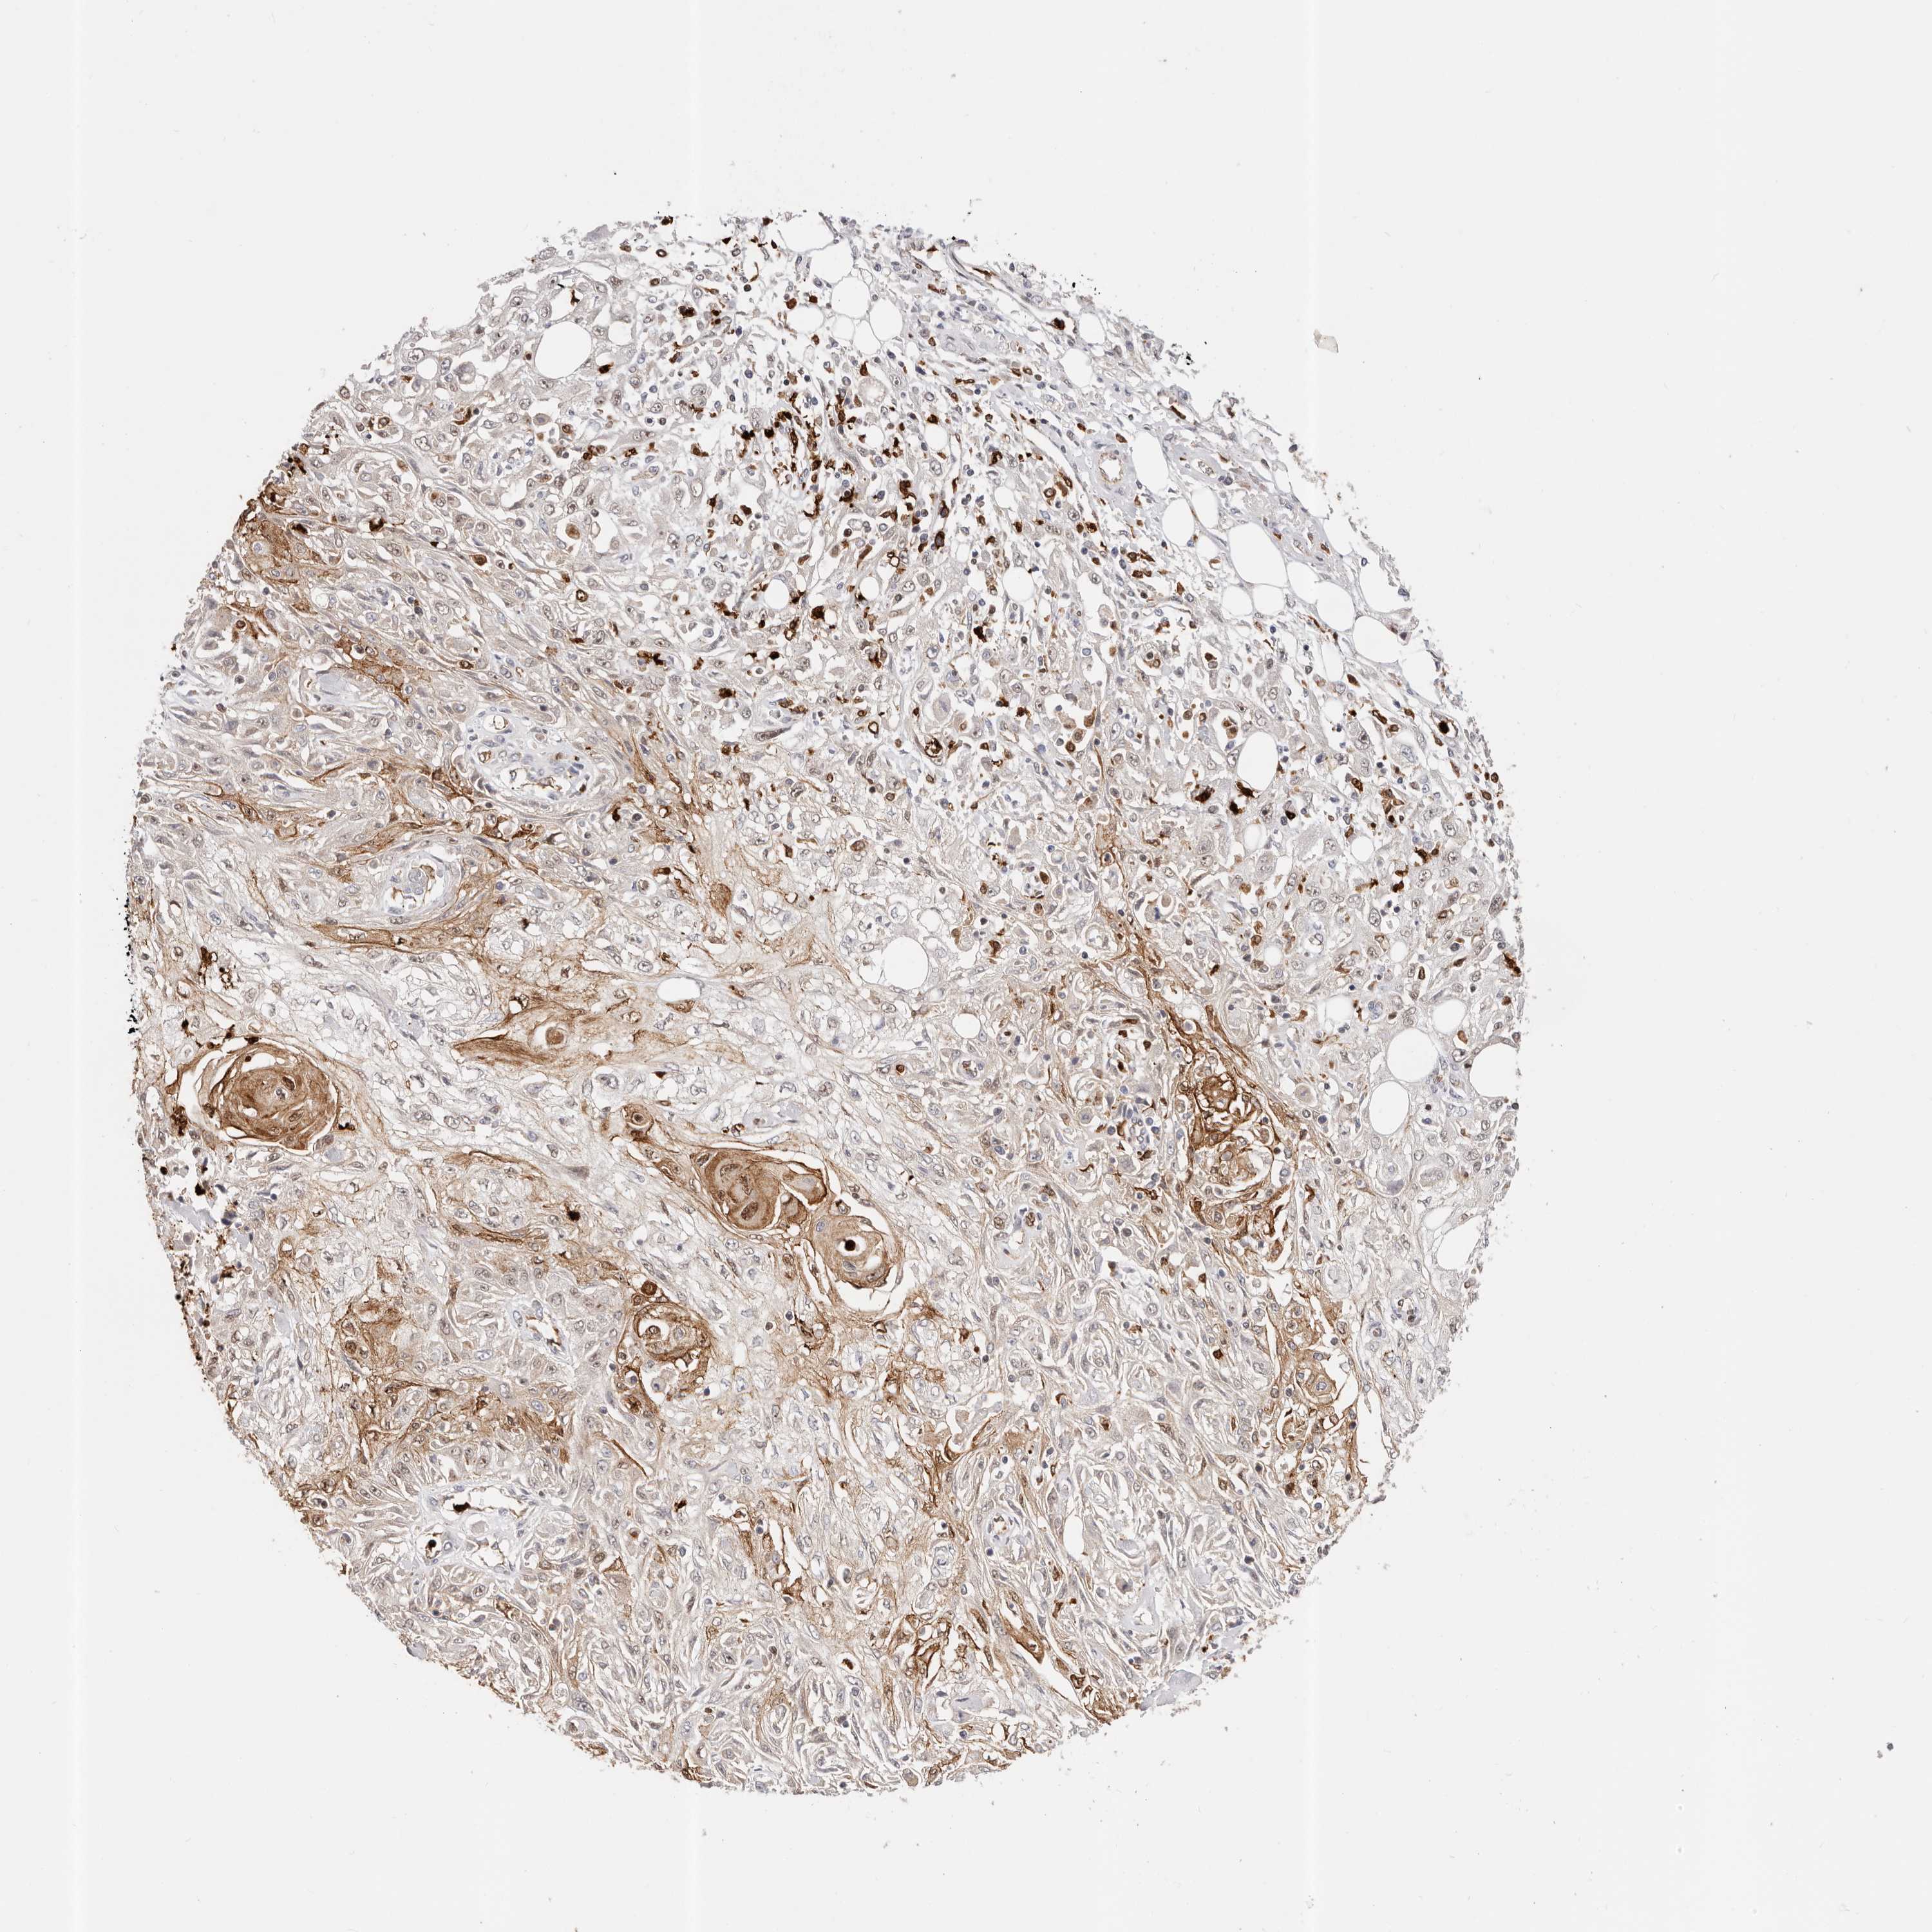

SKIN CANCER - Protein expressioni

A mouse-over function shows sample information and annotation data. Click on an image to view it in a full screen mode. Samples can be filtered based on level of antibody staining by selecting one or several of the following categories: high, medium, low and not detected. The assay and annotation is described here.

Each image is clickable and will lead to virtual microscopy that enables deeper exploration of all samples and also displays staining intensity scores, fraction scores and subcellular localization as well as patient and tissue information for each sample.

HPA030212

HPA030213

HPA030214

HPA030215

CAB013496

Basal cell carcinoma

Squamous cell carcinoma, NOS

Squamous cell carcinoma, metastatic, NOS

Adnexal tumor, benign